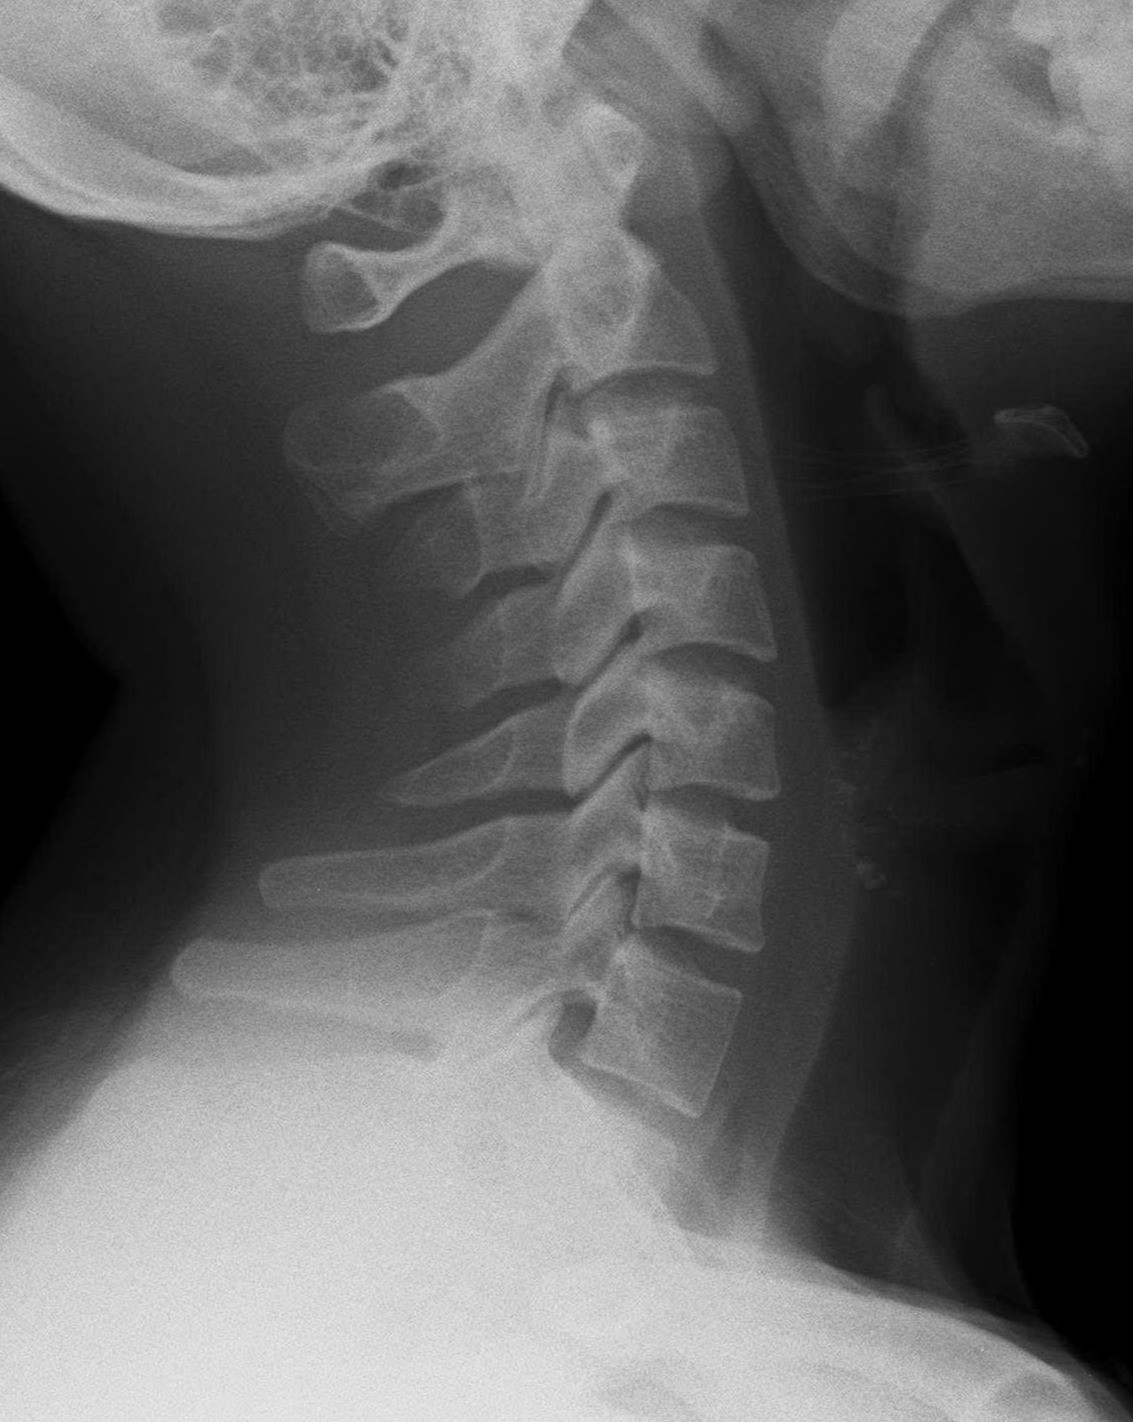

Kết quả chụp X-quang cho thấy cột sống cổ của bệnh nhân mất độ cong sinh lý, khiến các đốt sống cổ gần như xếp dọc thay vì có độ ưỡn ra trước như bình thường.

Tiến sĩ, bác sĩ Ngô Thị Kim Oanh - Phó Trưởng khoa Châm cứu - Dưỡng sinh, Bệnh viện Đại học Y Dược TPHCM - Cơ sở 3 cho biết, ở người trưởng thành khỏe mạnh, cột sống cổ có độ cong nhẹ về phía trước - gọi là độ ưỡn sinh lý giúp phân bổ đều lực từ đầu xuống vai và thân trên, hấp thu lực chấn động từ các hoạt động thường ngày (đi, đứng, chạy...), giảm tải trọng lên đĩa đệm và khớp liên đốt sống

Khi đường cong này bị mất, cột sống trở nên “thẳng như cây gậy” - làm tăng áp lực lên các đĩa đệm, khớp, dây chằng và cơ quanh cổ. Về lâu dài, điều đó có thể dẫn đến thoái hóa sớm, thoát vị đĩa đệm cổ, chèn ép rễ thần kinh hoặc tủy sống, gây ra các triệu chứng như đau, tê tay, chóng mặt, thậm chí yếu cơ.